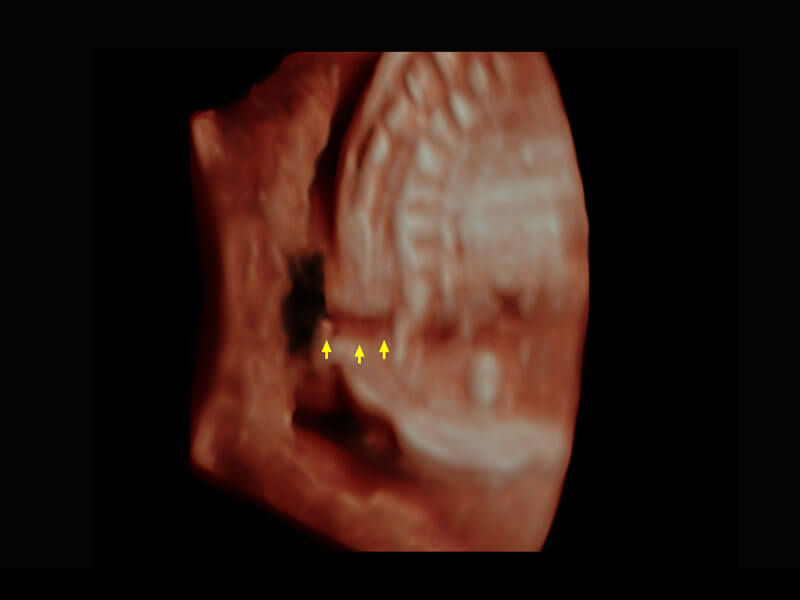

胎心筛查

P60搭载一系列胎儿心脏成像技术,实现精细的胎儿心脏评估。

• 右室双出口

• 胎心容积成像